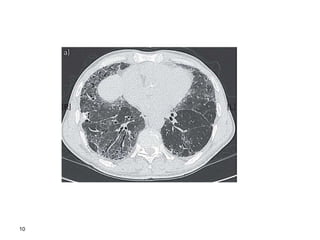

8

9

10

or cryobiopsy Thorax 2008;63(SupplV):v1– v58. doi:10.1136/thx.2008.101691 Diagnostic Algorhithm for ILD cryobiopsy